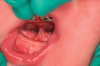

(3.) Preoperative and postoperative retracted views of a case involving an excessive tongue-tie that was treated with laser surgery.

Figure 3

Lasers can provide a highly effective means of treating tethered oral tissues. However, without water cooling, slight charring can occur. Slow and steady motions across the target tissue facilitate rapid ablation with minimal bleeding. Lingual frenulum ablation should permit the tongue to raise and freely extend forward without cupping or curling at the tip (Figure 3 and Figure 4). In many cases, the tongue will almost immediately increase its extension as the tie is released. Regarding the labial frenulum, releases should permit the upper lip to protrude forward adequately enough to develop a proper seal and a more stable latch around a nipple or pacifier (Figure 5 through Figure 7).